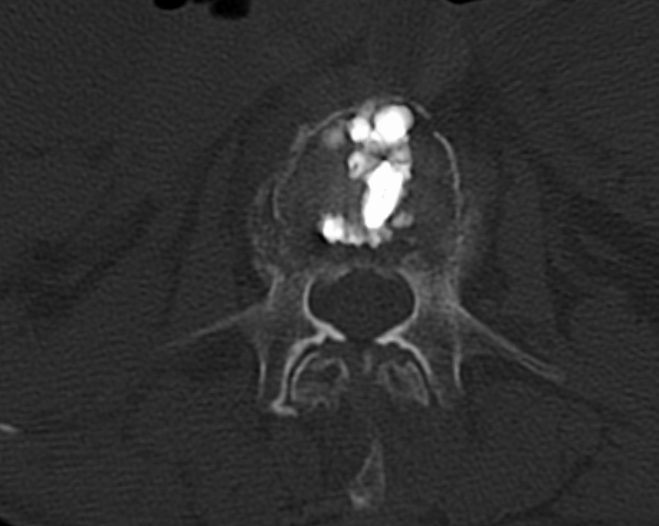

十余年来,我科室相继开展骨质疏松症的相关诊治工作,逐渐形成了自身的诊治体系,后经过整合联系,形成了以骨科二病区为龙头,联合检验科、放射科、内分泌科、血液风湿科等多学科结合、内外协作的骨松诊治MDT模式。目前采用的诊断方式有血钙及维生素ADKE检测、双能X线骨密度检测等,治疗方面也内外兼修,既可应用促成骨的四烯甲萘醌等,抑制骨吸收的唑来膦酸等药物治疗,又可采取椎体强化术、经皮穿刺椎弓根钉置入术等有效手术治疗,可结合患者自身情况,采取合适的治疗手段。开展骨质疏松诊治工作的十几年来,遵循指南,结合当地实际,总结归纳出了一套立足自身实际的诊疗体系,采取药物治疗与手术治疗相结合、因人而宜、综合施治的个体化的综合诊疗方案等。近年来,随着微创理念的推行和ERAS理念的实践,骨科二病区率先在本地区开创性的应用微创经椎间孔入路椎体强化术、经皮穿刺椎弓根钉置入术等先进治疗手段,实现立竿见影的治疗效果,深得广大患者的好评,取得了良好的社会效益和学术影响力,使桓台百姓足不出县即可享受到国内外先进的脊柱外科诊治体验。

术后术前